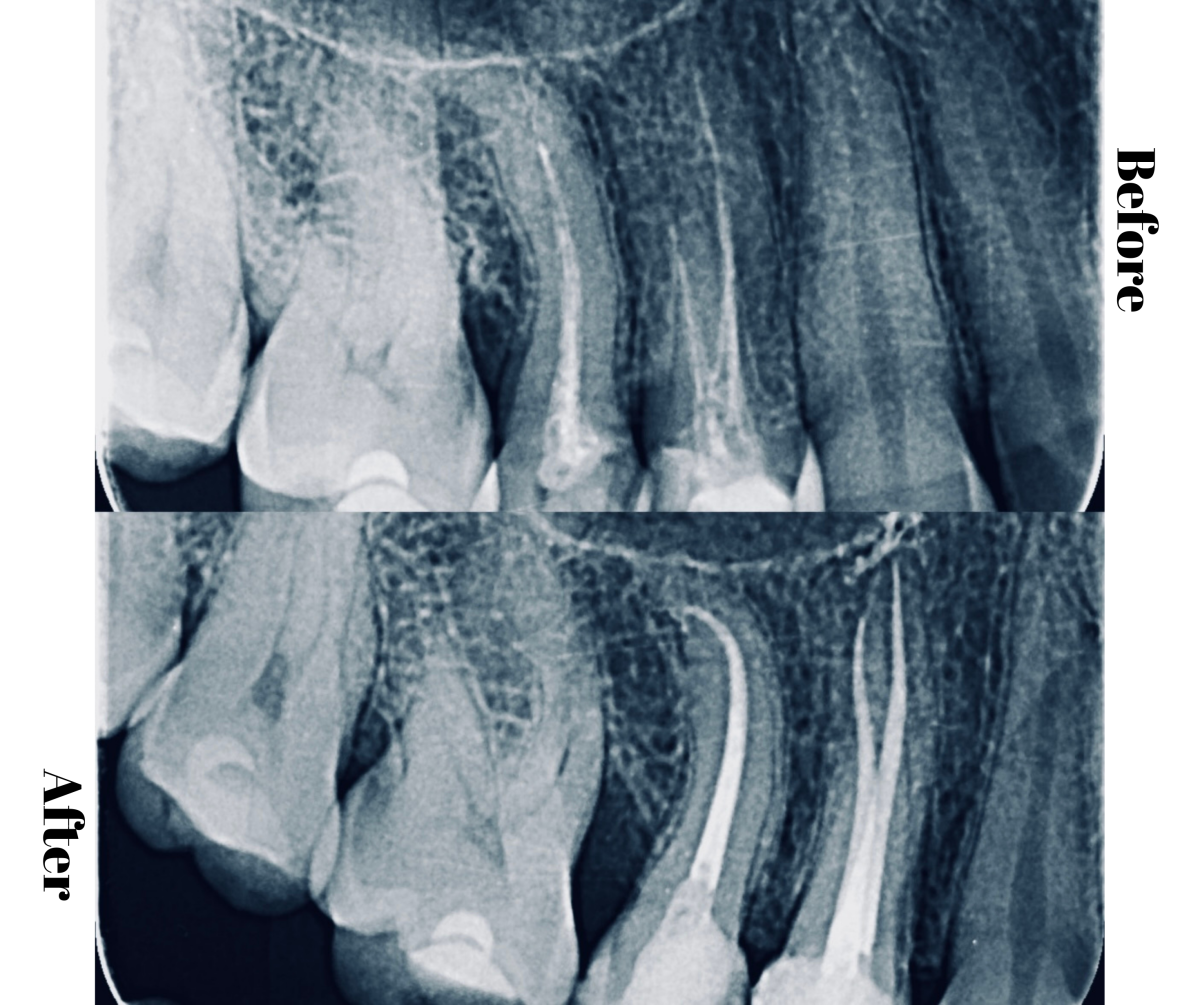

Parodontită apicală acută, tratament de canal anterior

Parodontită aplicală acută, abces

Parodontită apicală acută, asociată cu tratament de canal anterior